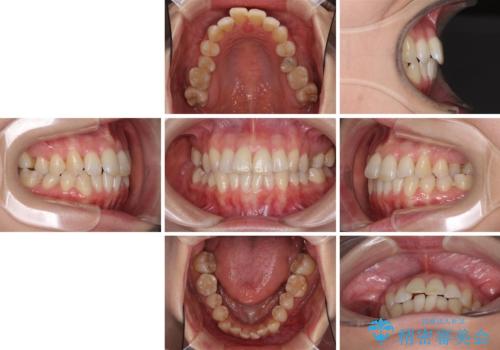

急速拡大装置で奥歯の咬み合わせを改善 インビザラインによる矯正治療

- 奥歯の咬み合わせを気にして来院された患者様です。

上顎骨の幅が下顎骨よりも小さいので、拡大装置により骨幅を広げて上下関係を改善し、その後インビザラインにて歯並びを整えることとしました。

上下の骨幅を改善したことで、スムーズに歯列矯正を行うことができました。

奥歯の咬み合わせを改善する必要があったため、治療は長期化しましたが、きっちりと仕上げることができました。